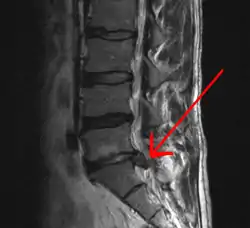

In most episodes of low back pain, a specific underlying cause is not identified or even looked for, with the pain believed to be due to mechanical problems such as muscle or joint strain.[1][4] If the pain does not go away with conservative treatment or if it is accompanied by "red flags" such as unexplained weight loss, fever, or significant problems with feeling or movement, further testing may be needed to look for a serious underlying problem.[5] In most cases, imaging tools such as X-ray computed tomography are not useful or recommended for low back pain that lasts less than 6 weeks (with no red flags) and carry their own risks.[9] Despite this, the use of imaging in low back pain has increased.[10] Some low back pain is caused by damaged intervertebral discs, and the straight leg raise test is useful to identify this cause.[5] In those with chronic pain, the pain processing system may malfunction, causing large amounts of pain in response to non-serious events.[11]

An intervertebral disc has a gelatinous core surrounded by a fibrous ring.[36] When in its normal, uninjured state, most of the disc is not served by either the circulatory or nervous systems – blood and nerves only run to the outside of the disc.[36] Specialized cells that can survive without direct blood supply are in the inside of the disc.[36] Over time, the discs lose flexibility and the ability to absorb physical forces.[27] This decreased ability to handle physical forces increases stresses on other parts of the spine, causing the ligaments of the spine to thicken and bony growths to develop on the vertebrae.[27] As a result, there is less space through which the spinal cord and nerve roots may pass.[27] When a disc degenerates as a result of injury or disease, the makeup of a disc changes: blood vessels and nerves may grow into its interior and/or herniated disc material can push directly on a nerve root.[36] Any of these changes may result in back pain.[36]

Imaging is indicated when there are red flags, ongoing neurological symptoms that do not resolve, or ongoing or worsening pain.[5] In particular, early use of imaging (either MRI or CT) is recommended for suspected cancer, infection, or cauda equina syndrome.[5] MRI is slightly better than CT for identifying disc disease; the two technologies are equally useful for diagnosing spinal stenosis.[5] Only a few physical diagnostic tests are helpful.[5] The straight leg raise test is almost always positive in those with disc herniation,[5] and lumbar provocative discography may be useful to identify a specific disc causing pain in those with chronic high levels of low back pain.[44] Therapeutic procedures such as nerve blocks can also be used to determine a specific source of pain.[5] Some evidence supports the use of facet joint injections, transforminal epidural injections and sacroiliac injections as diagnostic tests.[5] Most other physical tests, such as evaluating for scoliosis, muscle weakness or wasting, and impaired reflexes, are of little use.[5]